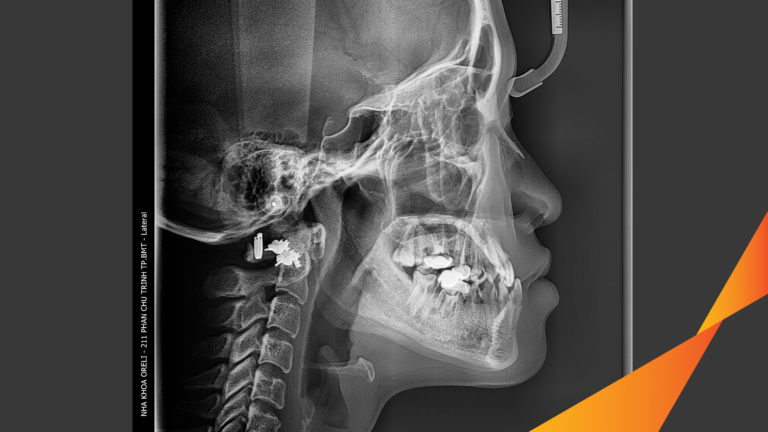

Ca niềng răng đặc biệt: kéo răng 7, 8 thay thế 3 răng 6 bị hư tại Oreli Niềng răngDi gần răng 7 8 Xem thêm